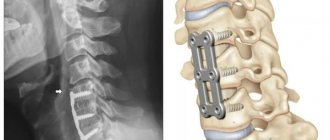

• stenting - a stent is placed inside the vessel to expand and strengthen the walls;

· Stenting. The vessel is expanded with stents - springy or mesh devices.